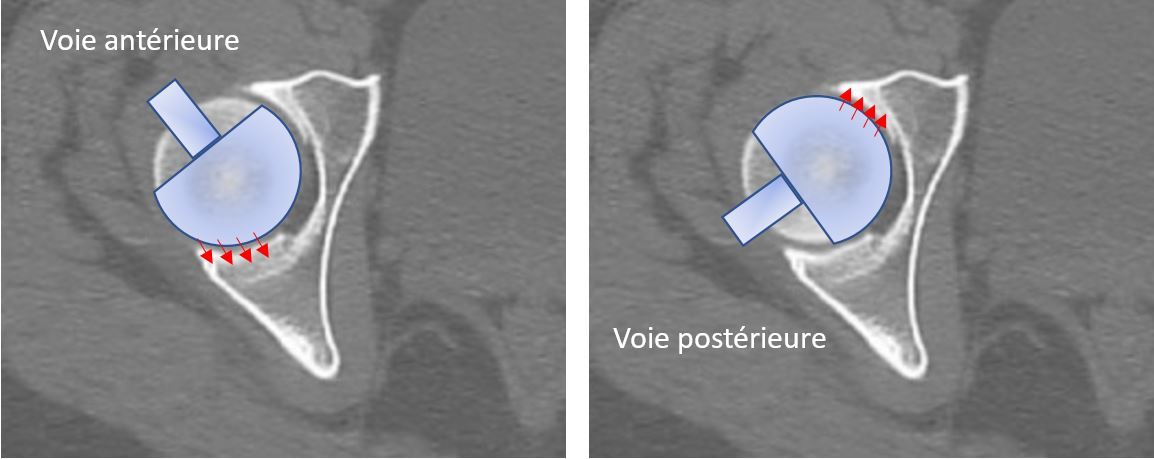

Reamer positioning may be influenced by the approach route: anterior routes may favour preferential reaming of the posterior column, while posterior routes may favour preferential reaming of the anterior column (Fig. 3).

Figure 3: Impact of the approach route on reaming of the acetabulum.